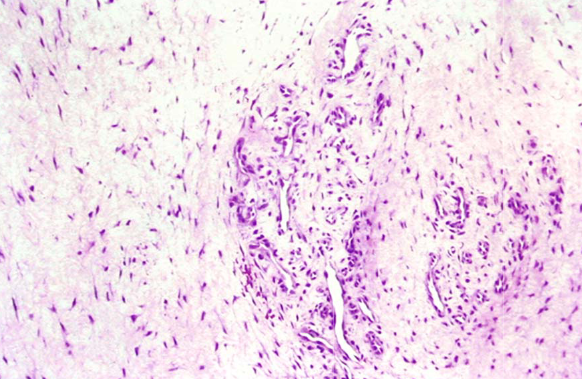

На гистопатологическом уровне наблюдаются изменения в молекулярной структуре сухожилия, часто связанные с расщеплением и дегенерацией коллагена.

на изображении схематично показано тандинопатия сухожилия голнесотопного сустава